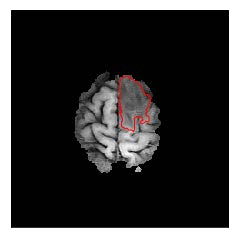

Machine learning has been widely adopted for medical image analysis in recent years given its promising performance in image segmentation and classification tasks. The success of machine learning, in particular supervised learning, depends on the availability of manually annotated datasets. For medical imaging applications, such annotated datasets are not easy to acquire, it takes a substantial amount of time and resource to curate an annotated medical image set. In this paper, we propose an efficient annotation framework for brain MR images that can suggest informative sample images for human experts to annotate. We evaluate the framework on two different brain image analysis tasks, namely brain tumour segmentation and whole brain segmentation. Experiments show that for brain tumour segmentation task on the BraTS 2019 dataset, training a segmentation model with only 7% suggestively annotated image samples can achieve a performance comparable to that of training on the full dataset. For whole brain segmentation on the MALC dataset, training with 42% suggestively annotated image samples can achieve a comparable performance to training on the full dataset. The proposed framework demonstrates a promising way to save manual annotation cost and improve data efficiency in medical imaging applications.

翻译:近年来,由于在图像分割和分类任务方面表现良好,医学图像分析广泛采用了机器学习。机器学习的成功,特别是监督学习的成功,取决于手动附加说明数据集的可用性。对于医疗成像应用来说,这种附加说明数据集不容易获得,需要大量的时间和资源来翻译附加说明的医学成像集。在本文件中,我们建议为大脑MR图像建立一个高效的注释框架,为人类专家提供信息性样图像,供人类专家作说明。我们评估了两种不同的大脑图像分析任务的框架,即脑肿瘤分割和整个大脑分割。实验显示,对于BRATS 2019数据集的脑肿瘤分割任务,培训一个只有7%的附加说明图像样本的分解模型,其性能与全数据集培训的性能相当。对于MALC数据集的整个大脑分割,用42%的附加说明性图像样本进行的培训,可以实现与全数据集培训的类似性能。拟议的框架展示了节省人工注解成本和提高医疗成像应用数据效率的有希望的方法。